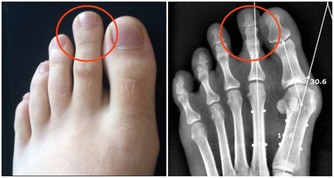

一般來說,額外的一小段臍帶會慢慢脫落、縮回,和腹部融合在一起便形成肚臍眼;「凸肚臍」是因為多出來的表皮組織無法完好地與腹部肌肉融合在一起所形成、或是臍疝氣所造成,但凸肚臍並不會對健康造成影響。